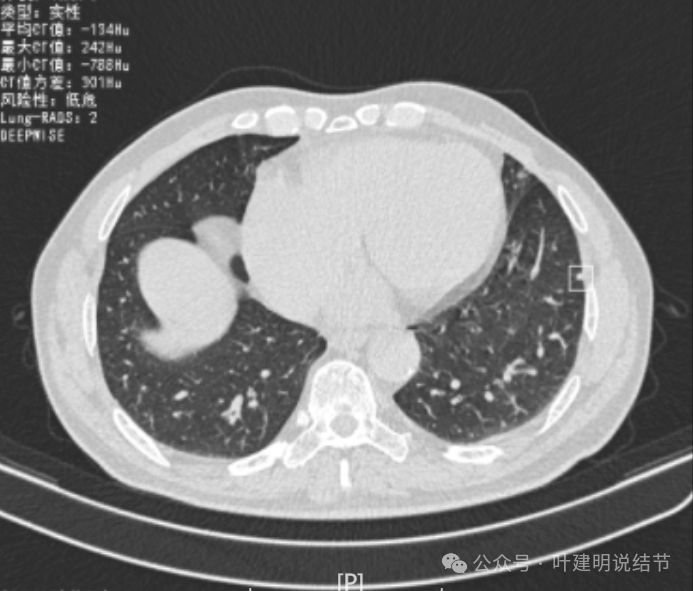

再看2024年6月时的影像:

右上没有明显变化,仍考虑良性可能性大。

左下也考虑良性,与2022年无明显变化。

右下新增病灶,混合密度,整体轮廓较清,瘤肺边界欠清。

有小血管进入,边缘毛糙。

局部有毛刺,但不够锐利;病灶感觉有一层晕似的,邻近胸膜下也有淡磨玻璃影。

实性密度为主,周围少许很淡的磨玻璃影。

边缘不平有毛刺,但不锐利;贴着胸膜但无明显牵拉。局部表面有浅分叶似的,但总体膨胀感不够。

病灶表面不光滑,边上有晕,邻近有淡磨,贴着胸膜无牵拉。

病灶边缘欠清晰,瘤肺边界稍模糊。较宽的基底贴着胸膜。

病灶有血管进入,有浅分叶,实性为主,邻近胸膜有片状淡磨玻璃影,近胸膜无牵拉。但有一定膨胀性。

病灶实性,与血管关系较为密切。

血管走向病灶,但似乎没有被病灶影响,有向内侧的分支甚至没有哪怕一点凹向病灶侧。整体显得偏模糊。

边缘区域杂乱,边糊。